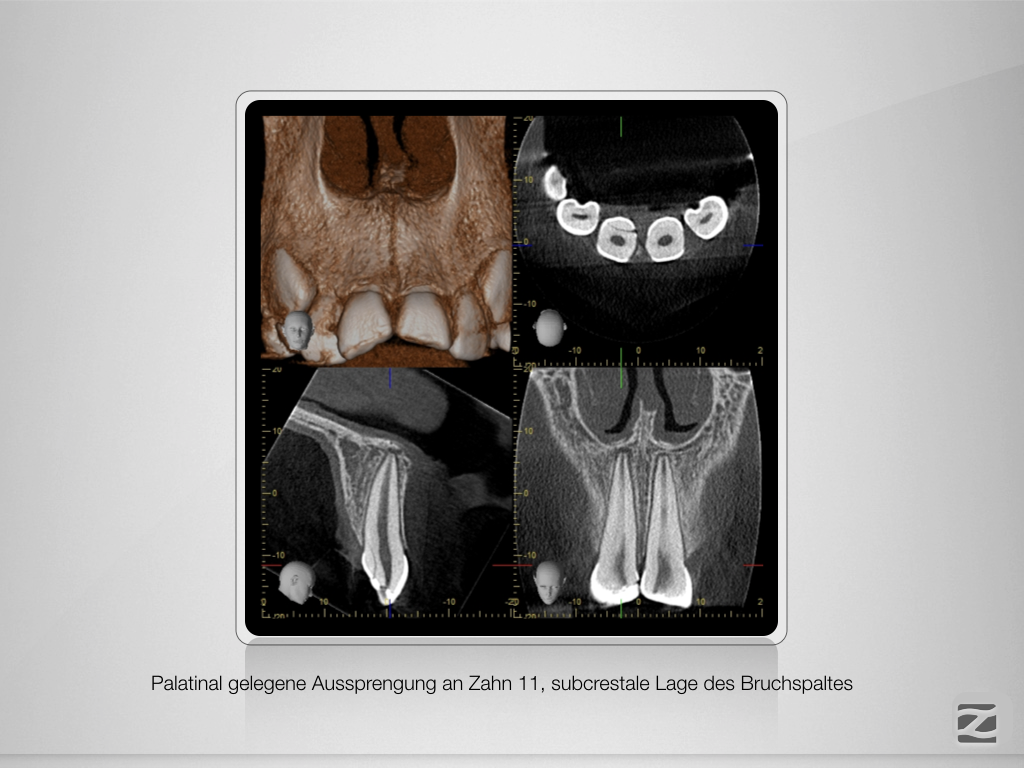

Frontzahntrauma – das klinische Vorgehen.